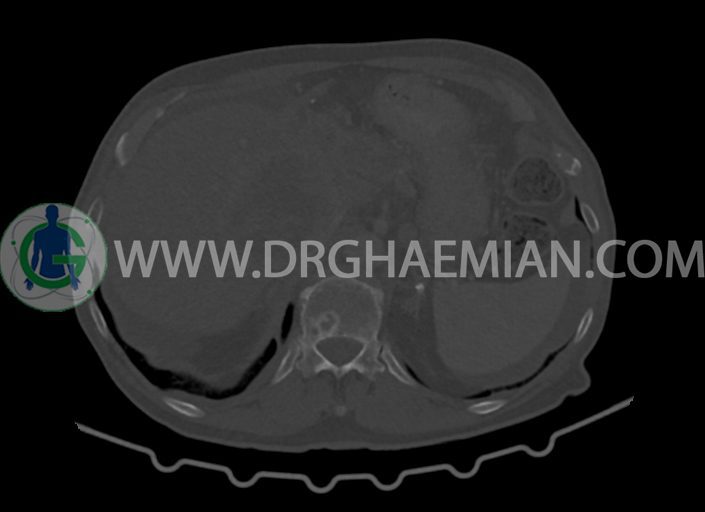

در سی تی اسکن اسپیرال شکم و لگن با کنتراست خوراکی و وریدی (مولتی دیدکتور 16 با مقاطع ظریف و بازسازی های ساژیتال و کرونال) :

-مایع آسیت با حجم Mild در ساب فرنیک دو طرف ، ساب هپاتیک و ساب اسپلنیک و اینترلوپ لگنپ

-توده ی بزرگ با حدود لبوله به ابعاد 89x87x76mm در لوب چپ کبد همراه با گسترش اکستراکپسولار و

شواهد آتروفی لوب جپ کبد

-توده به قطر 33mm در سگمان 6 کبد

-توده ی هیپودنس به ابعاد 30x21mm در ورید پورت خارج کبدی مطرح کننده ی Tumor thrombosis

در ارتباط با ضایعات کبدی در درجه ی اول متاستاز مطرح است. در تشخیص افتراقی با توجه به آتروفی لوب

چپ، mass forming cholangiocarcinoma نیز مطرح می گردد.